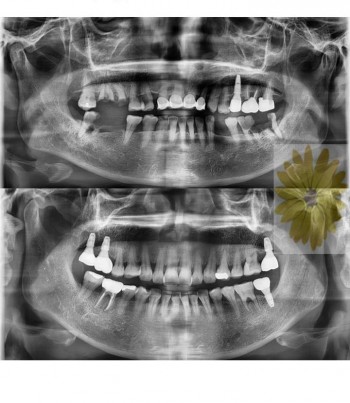

치료전후사진

민들레치과 치료 전후 사례

민들레치과 치료 전후사례